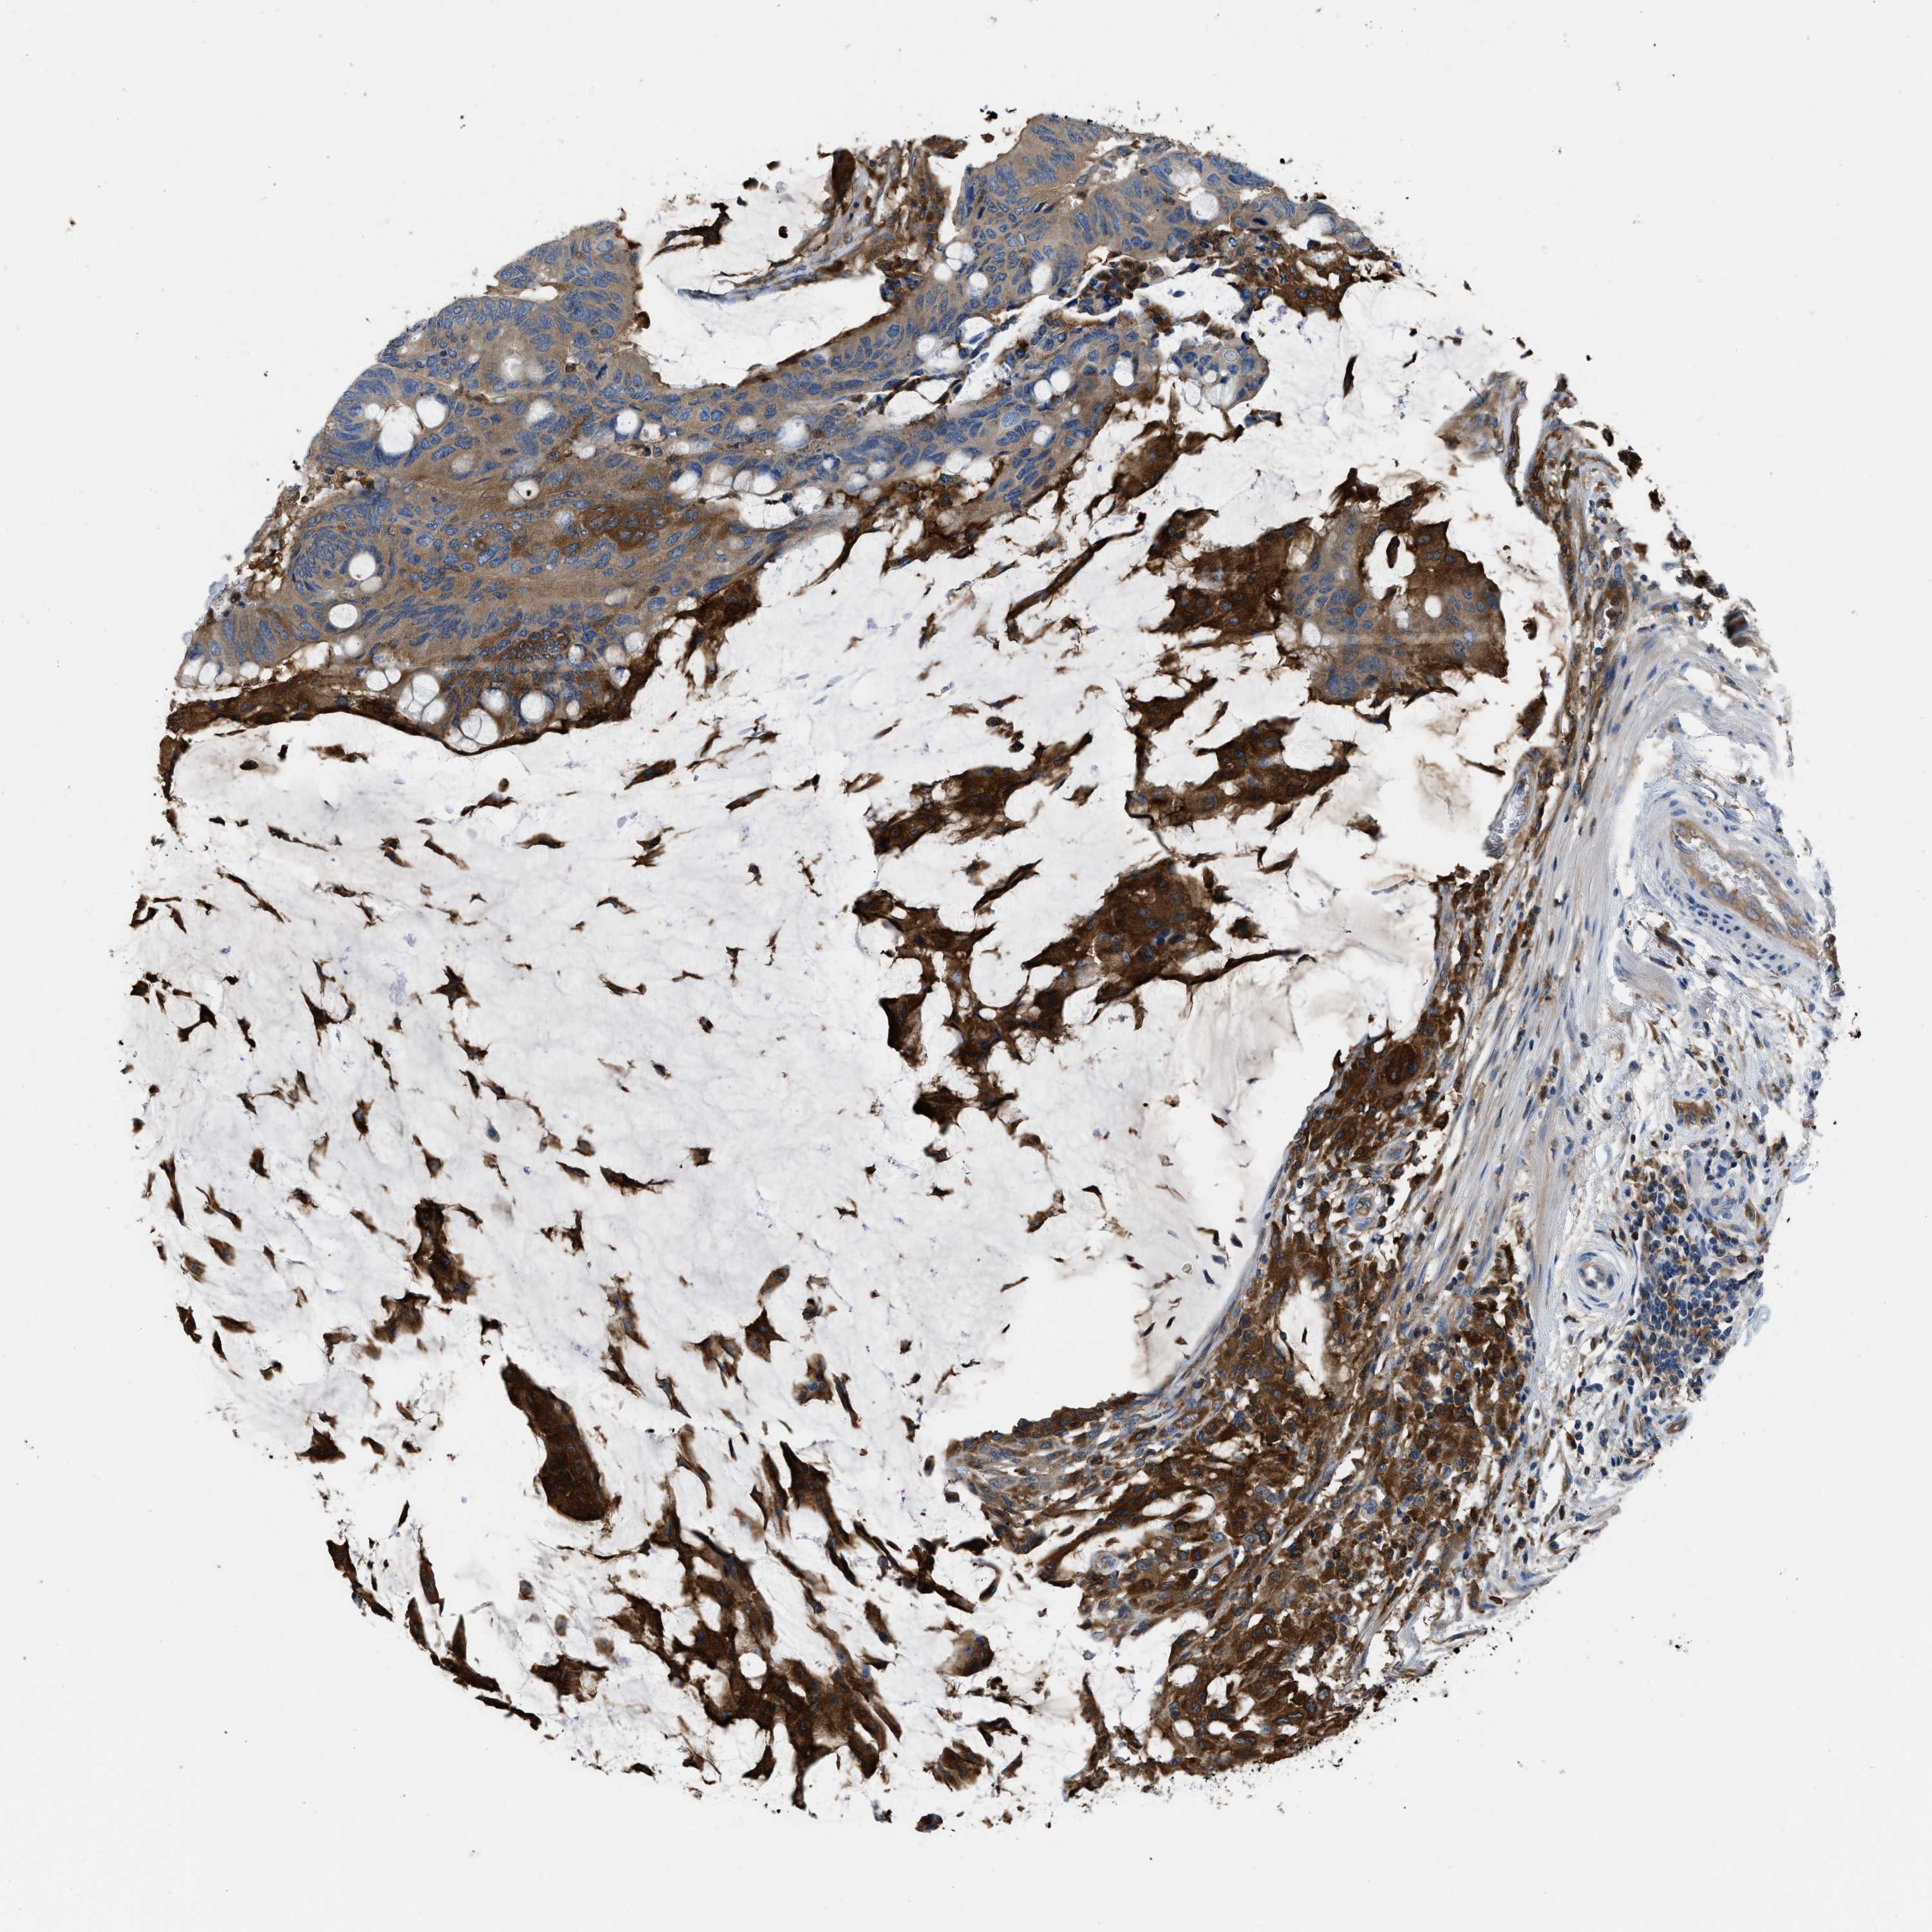

CANCER COLORECTAL CANCER Show tissue menu

Colorectal cancer

Human cancer

Colon adenocarcinoma